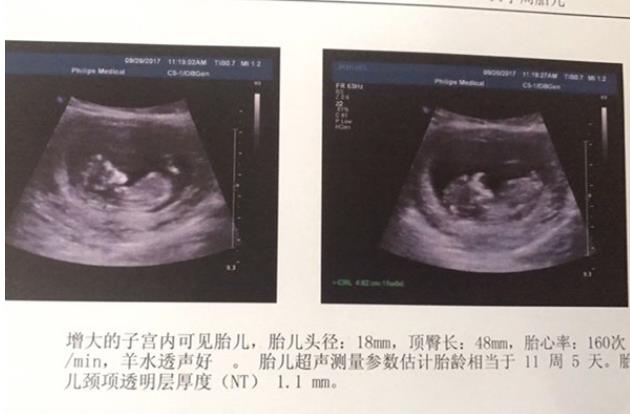

重庆妇幼试管和西南医院试管区别 做重庆试管婴儿如何提升卵子质量 ‘31周b超